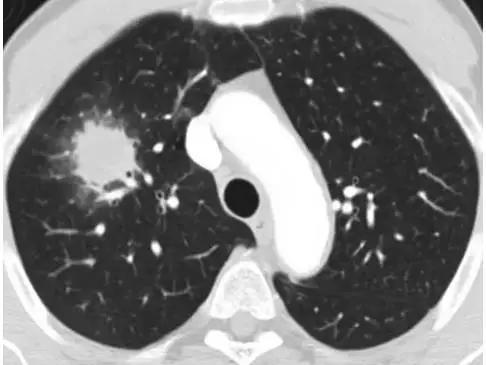

1.1   一 般 资 料   选 取 2020 年 3— 10 月本院收治 的 148 例 IPF 患者作为研究对象。纳入标准:符合 IPF 急性发作期诊断标准 [5] ;结合病史、血清学、 X 线片和高分辨率 CT 检查等确诊;近 1 个月内存 在不明原因的呼吸困难, 且肺功能呈急剧恶化状态; 气道分泌物和肺泡灌洗液经病原学诊断呈阴性;年 龄 >50 岁。排除标准:其他类型的肺部疾病;恶性 肿瘤;存在心脑血管病、血液疾病、严重的免疫性 疾病;肝肾功能障碍。患者及其家属对本研究内容了解并自愿签署知情同意书,且研究经本院伦理委员会批准(批准文号 020013)。按照随机数字表法分成观察组和对照组各 74 例。观察组男 43 例,女 31 例;年龄 51~83 岁,平均(65.34±3.60)岁;病程 5~9 个月,平均(7.06±0.72)个月;急性发作时间 2~6 d,平均(4.29±0.44)d;体质量指数(BMI)19~23 kg/ m2

1.3  观察指标  (1)比较两组临床疗效 [6]。显效:治疗后,咳嗽、咳痰及肺部啰音等症状体征消失,X 线片正常;有效:治疗后,咳嗽、咳痰及肺部啰音等症状体征有所减轻,X 线片或高分辨率CT 检查显示异常影像减少;无效:未达到上述标准。治疗总有效率 =(显效 + 有效)例数 / 总例数×100%。(2)比较两组治疗前后血气指标水平,包括动脉血氧分压(PaO2)、动脉血二氧化碳分压(PaCO2)和 pH,采用美国 MEDICA 公司生产的全自动血气分析仪测定。(3)比较两组不良反应发生率。